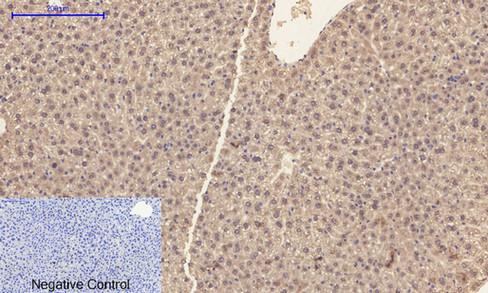

Specificity:Caspase-1 Polyclonal Antibody detects endogenous levels of Caspase-1

Dilution:IF 1:50-200 WB 1:500-2000, IHC 1:50-300, ELISA 1:10000-20000